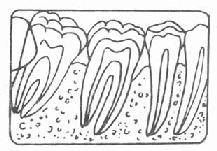

牙周袋形成:由于炎症的扩展,牙周膜被破坏,牙槽骨逐渐吸收,牙龈与牙根分离,使龈沟加深而形成牙周袋。可用探针测牙周袋深度。X线检查时可发现牙槽骨有不同程度的吸收。如图3-7~11.

| 图3-9 牙槽骨Ⅱ吸收 | 图3-10 牙槽骨Ⅲ吸收 |